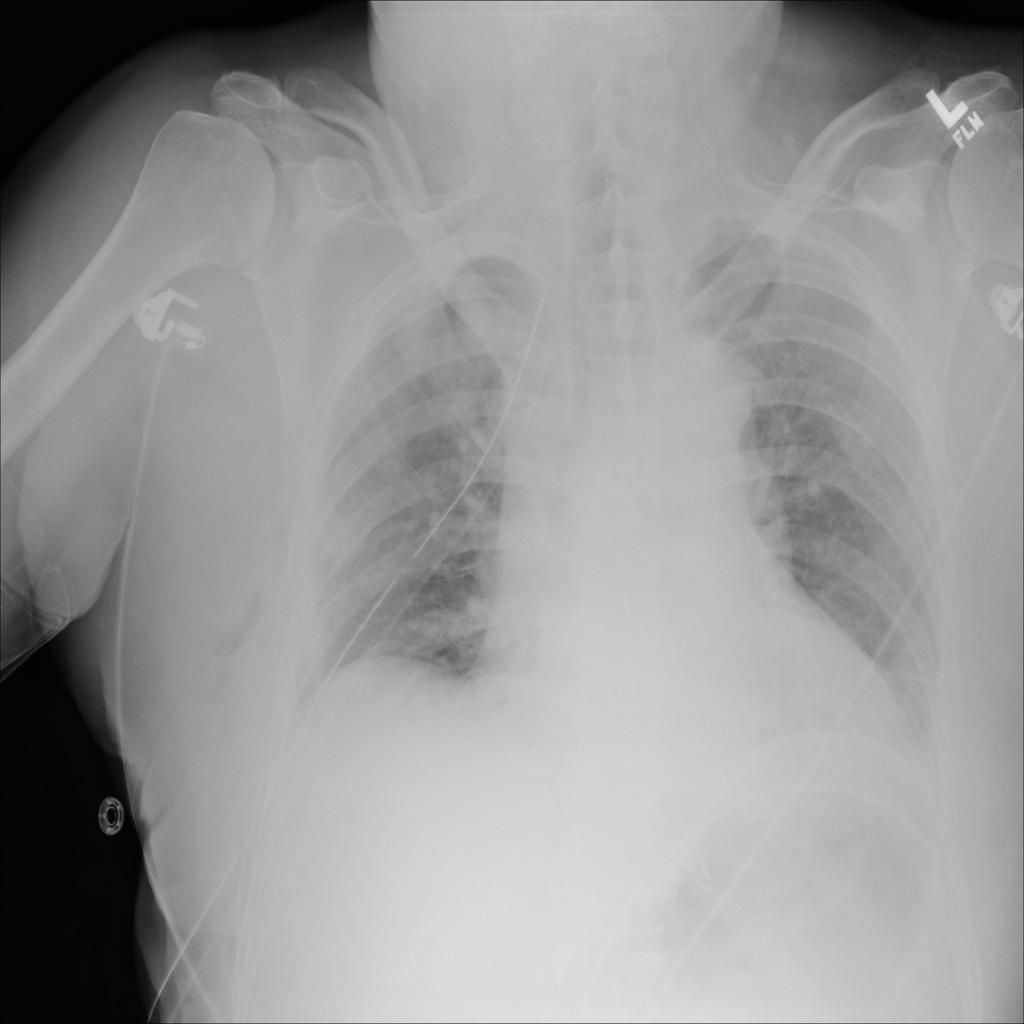

PAT-2A53 · IMG-004Emphysema

PAT-2A53 · IMG-004

AP